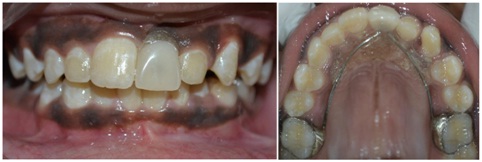

An 11-year-old boy accompanied by his parents reported to the Department of Pedodontics and Preventive Dentistry, with the chief complaint of tooth lost in the upper front region in a road accident. The parents reported the history of avulsion of left central incisor two years back. Intraoral examination revealed a mixed dentition, maxillary arch was oval in shape and maxillary right and left second premolars were buccally erupting. Mesio-buccal rotations were seen in maxillary second premolars and left maxillary canine. Class I molar relation on both sides and a 3 mm space loss in relation to 21. It was confirmed with IOPA [Table/Fig-8]. The case was undertaken for space regaining with modified 2 by 3 fixed appliances, followed by fixed functional space maintainer.

Intra oral photographs and IOPA

After two months follow-up, it was observed that the desirable space was gained, as showed in the IOPA [Table/Fig-10].

The brackets were debonded, an alginate impression was made bands were stabilized in impression and working cast was prepared. A modified Nance appliance was fabricated and replaced the lost tooth with an acrylic tooth [Table/Fig-11].

Modified Nance with acrylic tooth